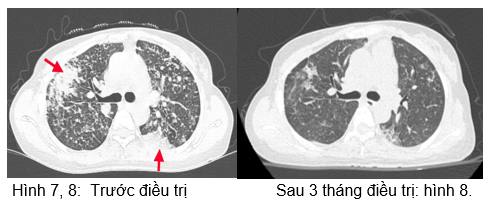

 Chụp cắt lớp vi tính lồng ngực:

Hình 9: Hình ảnh sau 6 tháng điều trị:  Các đám đông đặc và kính mờ 2 phổi (giảm số lượng và kích thước sau các đợt điều trị).